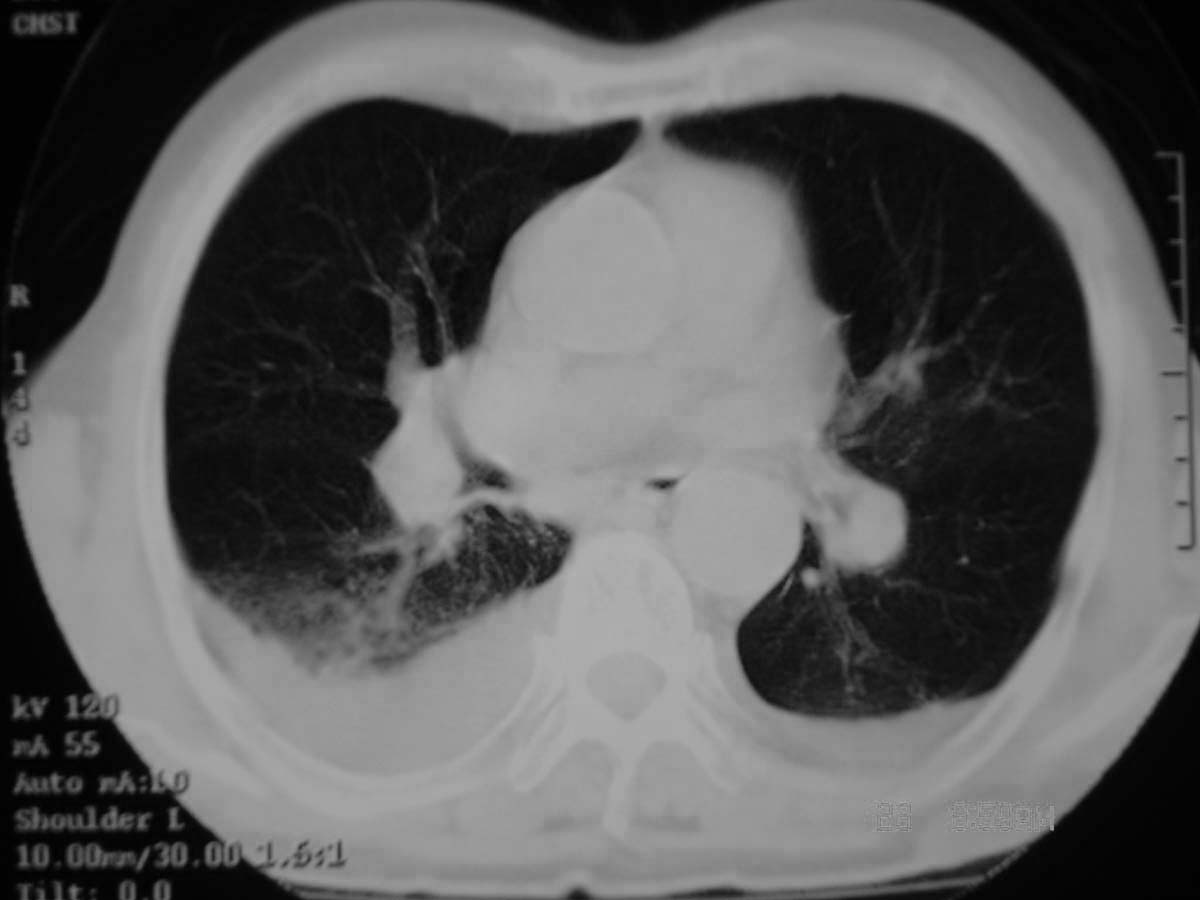

以下是引用守望可可西里在2006-11-23 14:33:00的发言:[br][br] 糖尿病病人很容易继发结核,病人又有双侧胸膜增厚、粘连、胸腔积液以及双上肺的斑片状、条索状影结核病灶影,以一元论考虑,右下肺病变首先考虑干酪性肺炎,可以正规抗炎治疗后复查,排除一般的肺炎。